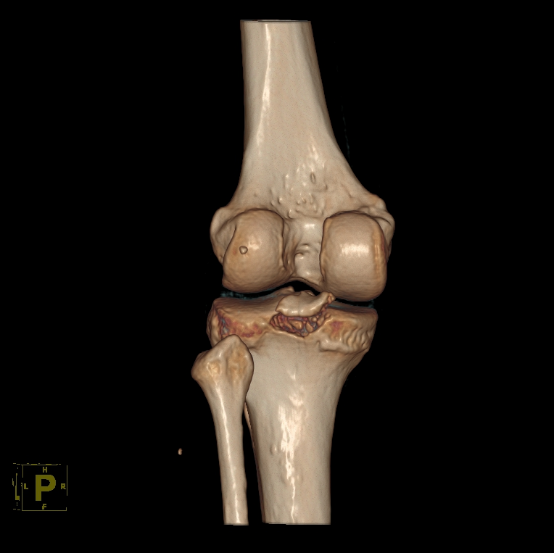

▲术前CT提示膝关节胫骨后交叉韧带止点撕脱骨折,

关节面不平